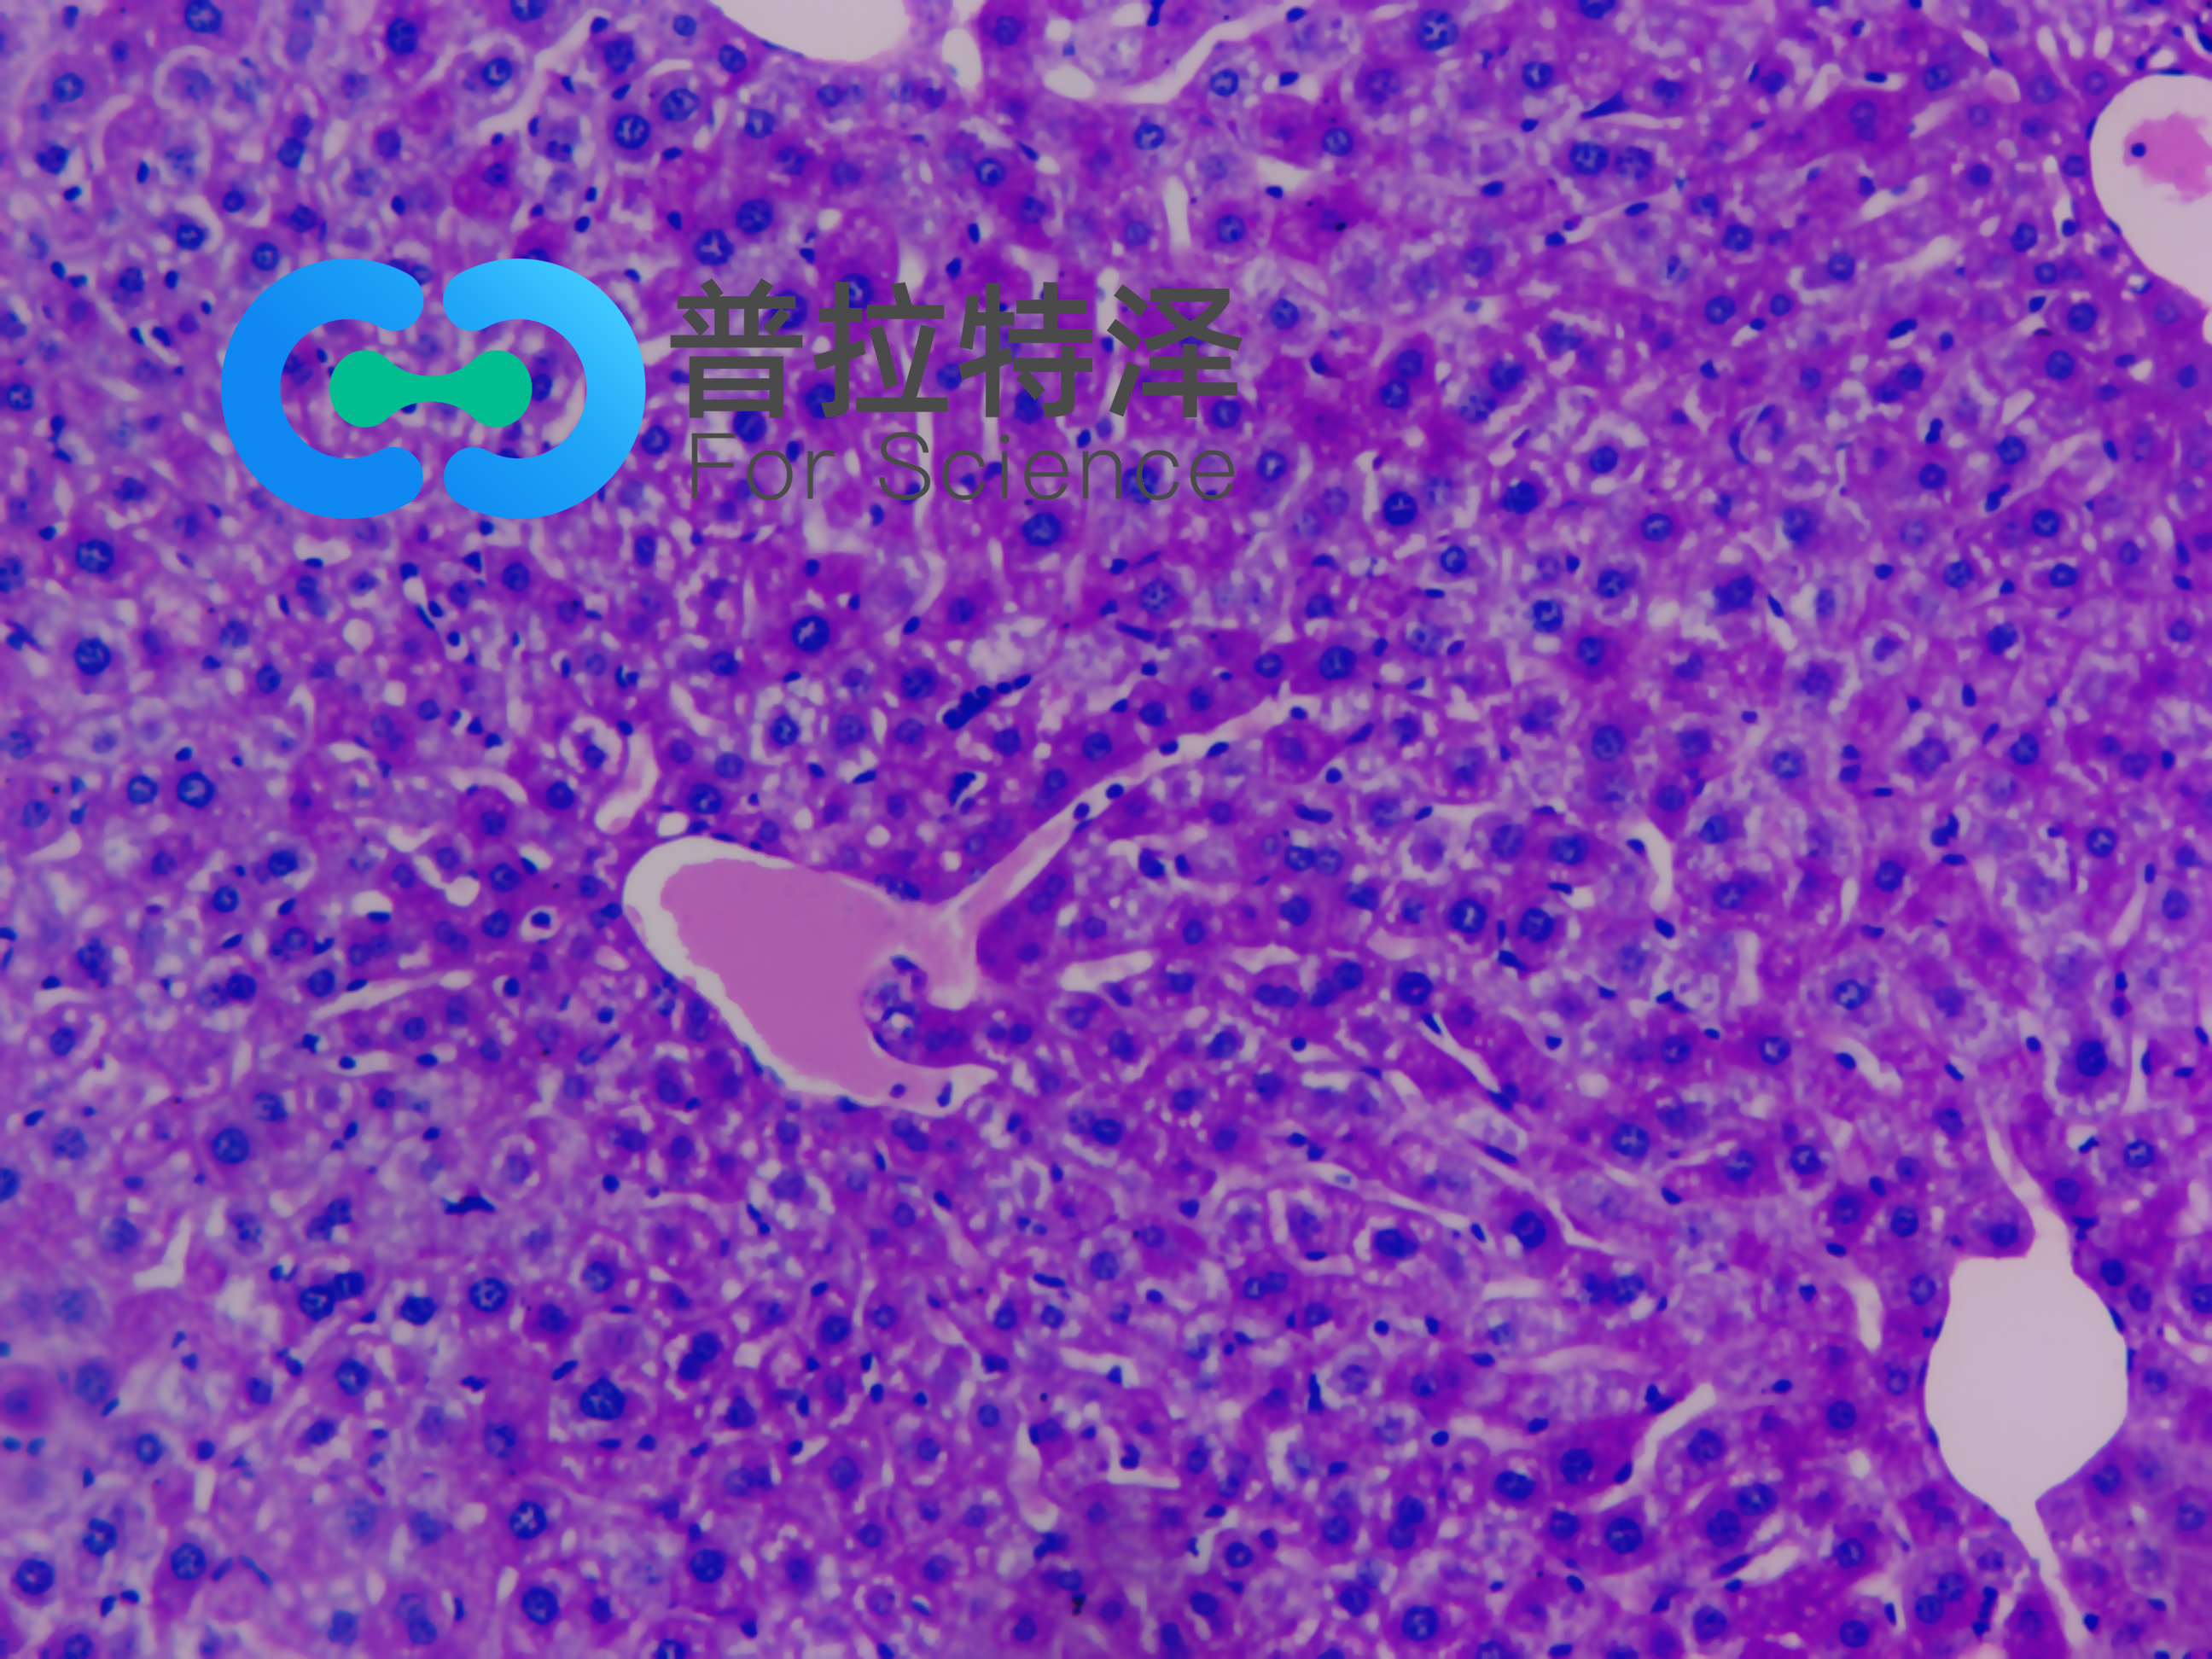

實(shí)驗(yàn)原理:糖原染色是病理學(xué)中常規(guī)的染色方法之一,氧化劑能氧化糖類(lèi)及有關(guān)物質(zhì)中的1,2-乙二醇基,使之變?yōu)槎┡cSchiff試劑能結(jié)合成一種品紅化合物,產(chǎn)生紫紅色。PAS技術(shù)常用來(lái)顯示糖原和其他多糖,該染色液不僅能夠顯示糖原,還能顯示中性黏液性物質(zhì)和某些酸性物質(zhì),以及軟骨、垂體、霉菌、真菌、色素、淀粉樣物質(zhì)、基底膜等。

隨著醫(yī)學(xué)實(shí)驗(yàn)技術(shù)的發(fā)展,近年來(lái),糖原染色應(yīng)用的范圍更加廣泛,如用以證明與鑒別細(xì)胞內(nèi)空泡狀的性質(zhì),心肌病變及其他心血管疾病的診斷,糖原累積病診斷和研究,糖尿病的診斷和研究,用于某些腫瘤的診斷等。除用于糖原的鑒定和黏液的顯示外,還可以觀察腎小球基底膜、結(jié)腸杯狀細(xì)胞中性黏液物質(zhì)、阿米巴滋養(yǎng)體和霉菌的著色。為臨床診斷、分類(lèi)和治療提供了重要的依據(jù)。